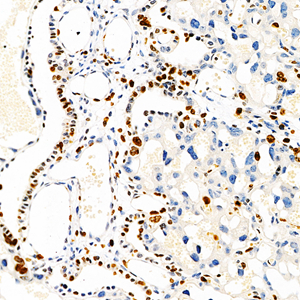

Images

| IHC analysis of Ki67 (GB111141). Sample: Mouse subcutaneous transplant tumor(H22) (Paraffin), 4% PFA (G1101) 12-24h. Antigen retrieval: Citrate buffer (pH 6.0) (G1201), pressure cooker 2min. Blocking buffer: 3% BSA in PBS (GC305010), RT, 30min. Primary antibody: 1: 500, 4°C overnight. Secondary antibody: HRP Goat Anti-Rabbit lgG (GB23303), 1: 200 RT 1h. |